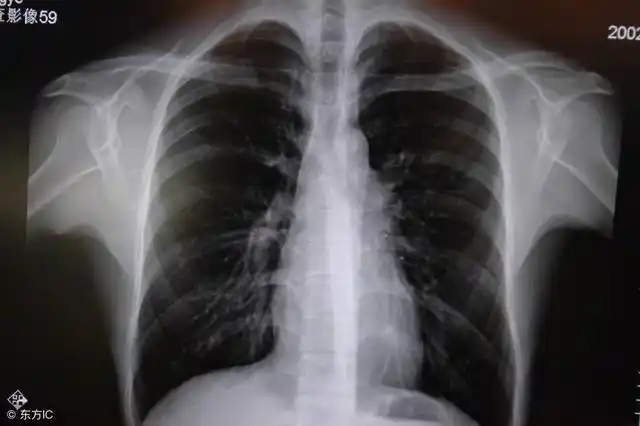

咳嗽3个月,发现肺部阴影1个月

胸部x光图片示肺部阴影图片来源: james heilman, md/wikipedia